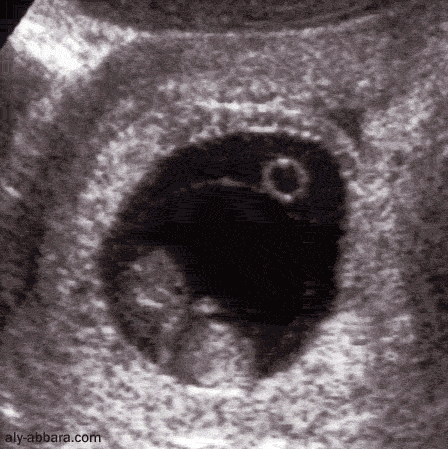

Grossesse de 9,5 semaines d'aménorrhée

(longueur crânio-caudale de 30 mm)